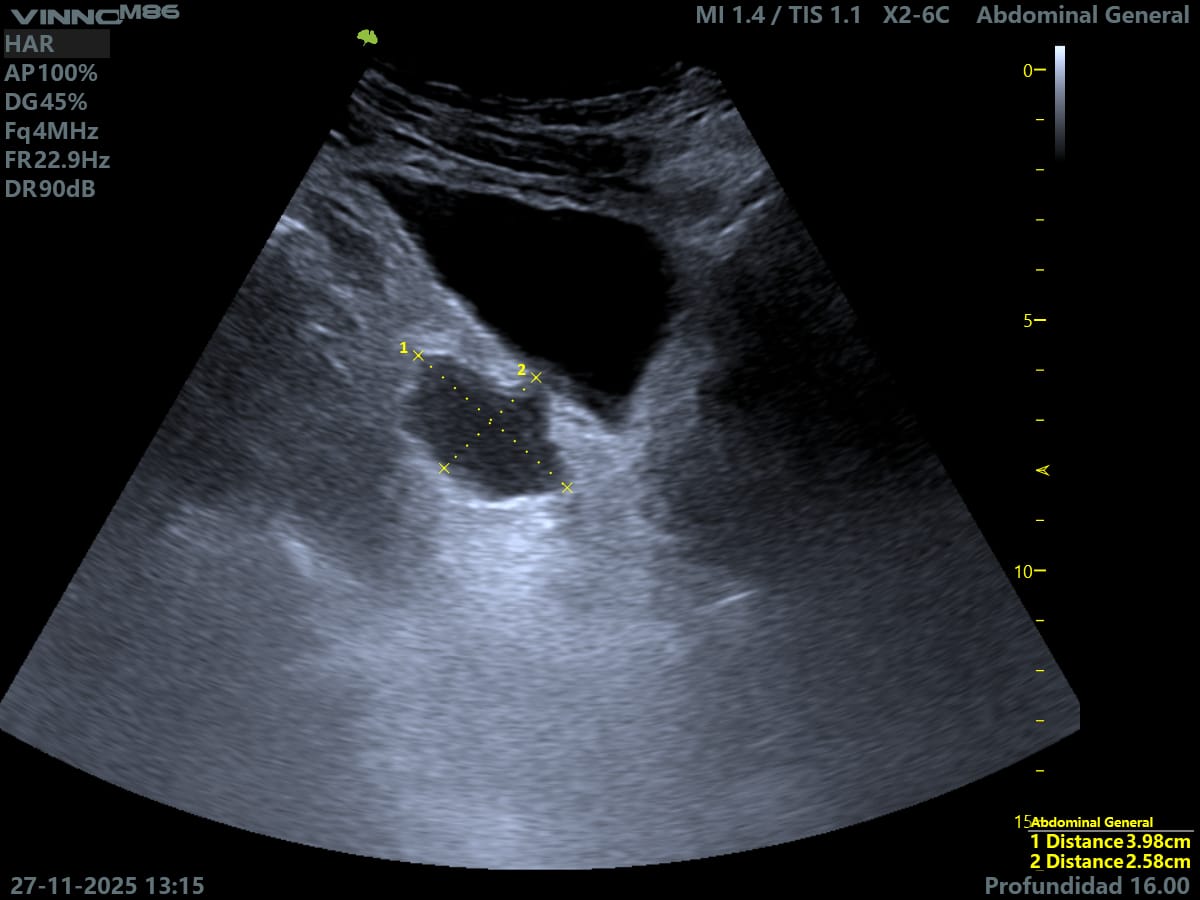

Ecografía: hipertrofia benigna de próstata con volumen de 60,48 cm cúbicos y divertículo vesical de 3,98 x 2,58 cm.